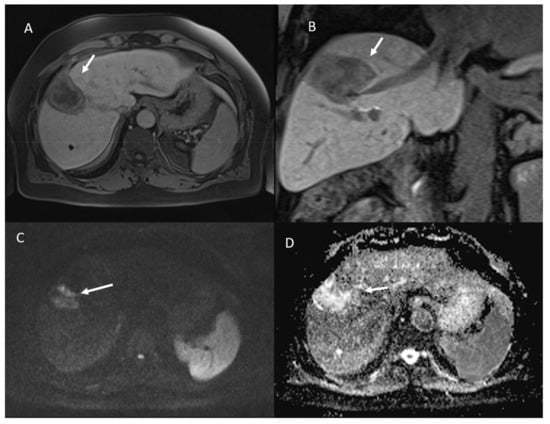

- 21 showed APHE and 2 rim APHE during arterial Phase (Figure 2).

- 23 showed wash-out appearance during portal phase and hypointense SI in equilibrium phase (Figure 2).

- 23 lesions were hyperintense in T2-W and hypointense in T1-W sequences (Figure 3).

- 23 lesions showed restricted diffusion with hypointense SI in ADC map (Figure 4).